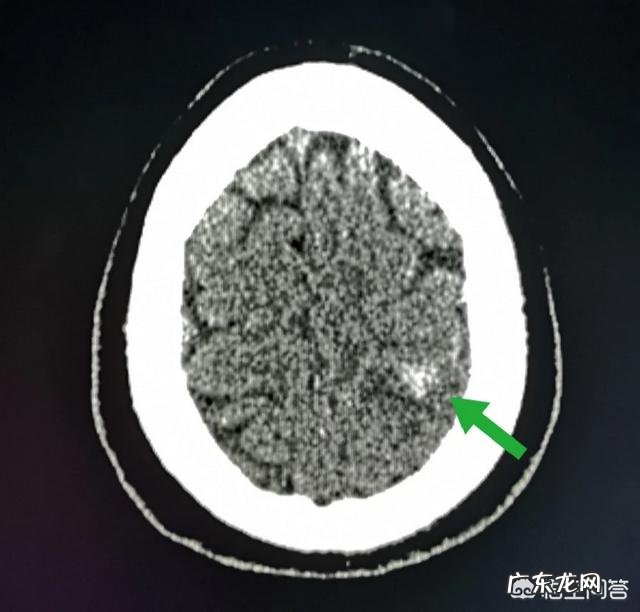

2.女性,28岁,白领这是一位令人心疼的病人,再生障碍性贫血,突发头疼一小时 。

脑CT发现左顶叶脑出血:

这已经是第2次发作了,因为血小板减少,凝血功能下降导致 。